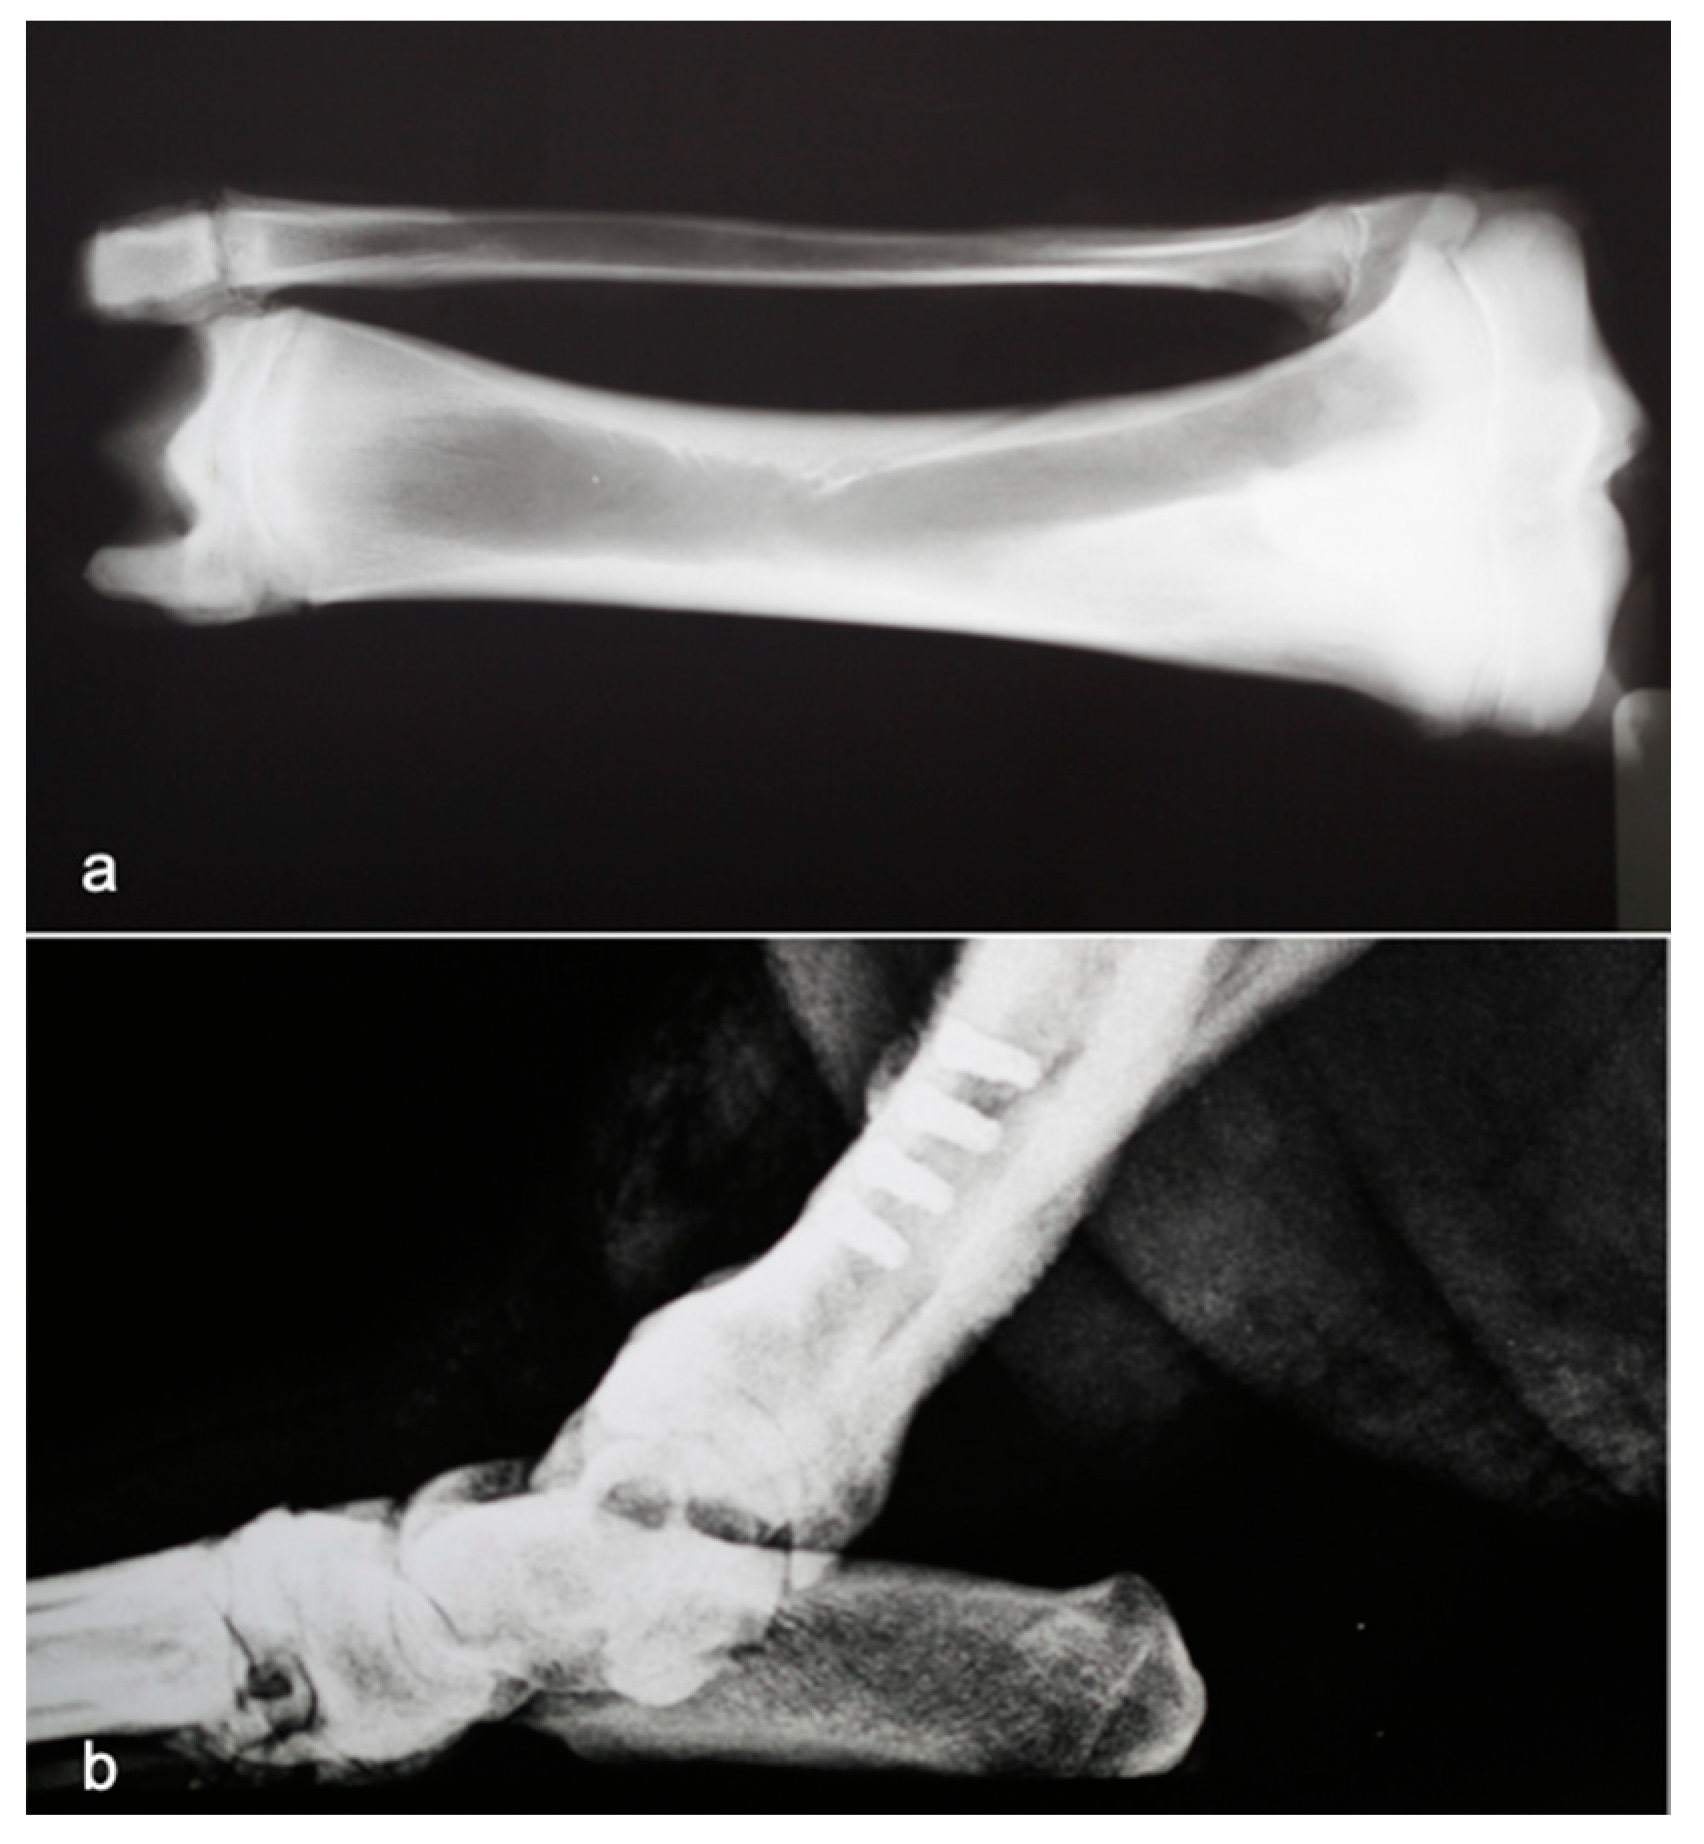

The right hind leg was prepared in a standard sterile fashion. The tibia was exposed, and the implant was inserted using a 45 N·cm torque by using the drilling technique according to the Brånemark protocol [19] (Figure 1).

Figure 1.

X-ray tibia of minipig showing the relationship between cortical and cancellous bone (a). X-ray tibia with implants (b).

The experimental design was based on the previous experience of the authors with this animal model, in which the anatomical characteristics of the tibia are similar to those of the human mandibular bone with regard to the cortical/cancellous relationship and the bone quality, as can be seen in Figure 1 [1,10,11].